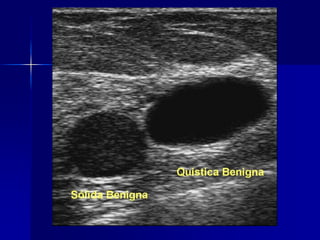

Sólida benigna y maligna

Benigna o maligna

 Sólida

 Quística

Fibroadenoma

Neoplasia Maligna

(Ca y otras)

Quiste mamario

(Raro Ca intraquístico)

Benigna o maligna Sólida  Quística Fibroadenoma Neoplasia Maligna (Ca y otras) Quiste mamario (Raro Ca intraquístico)